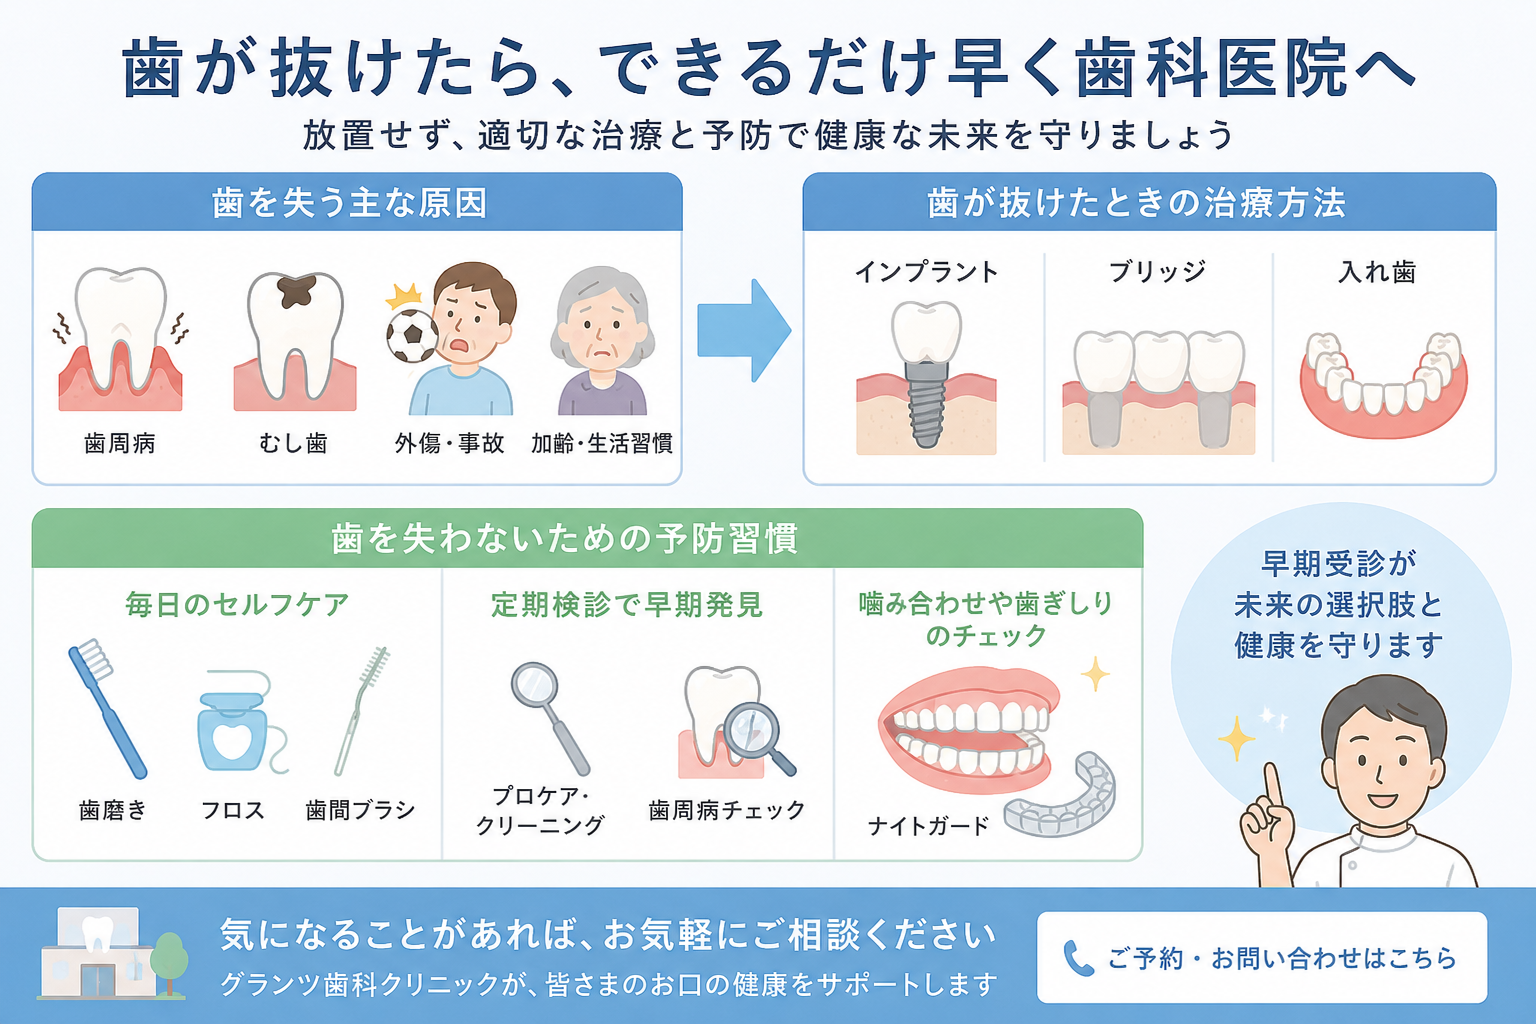

私は開業する前の職場で、たくさんインプラント治療を手がけてきました。インプラントは歯がなくなったところに、新しく歯が入るという画期的な治療法です。

私のイメージでは、どんなに頑張って、費用をかけて、高級な材料で、良い入れ歯を作っても、インプラントには勝てません。

なぜなら、動かないし、外れないし、よく噛めるからです。

そのため、患者さんはインプラントの悪いイメージを植え付けられてしまい、私の患者さんでも「インプラントは怖いからだめ」とおっしゃる方は少なくありませんでした。確かに怖い一面があります。インプラントを入れる行為は、「外科処置」であり、外科処置をほとんどしないような歯科医師がインプラントを簡単に入れたり、レントゲン設備(特にCT)を持たない歯科医院でのインプラント治療は失敗する確率が高いのではないでしょうか。しかし実際は、インプラントの正しい知識を持った歯科医師が施術を行えば、かなり高い確率の成功率があります。それを知らずにインプラントを治療の選択肢から外してしまう患者さんは可哀想だなと思っていました。

最近になりインプラントの悪い報道が減ってきたように思います。それは、歯科医師も患者さんも正しい知識を持つようになったからではないでしょうか。時代は進歩しており、インプラントのトラブルが出ないように、術前にシミュレーションを行い、骨の状況や神経、血管の位置を事前に把握することができます。そして手術の際には、シミュレーション通りにインプラントが入るように、3Dプリンターを利用した手術用の補助器具も一般的になりました。その恩恵でインプラント手術にかかる時間は大幅に短縮され、歯科医師、患者さんともに安心できるようになってきました。